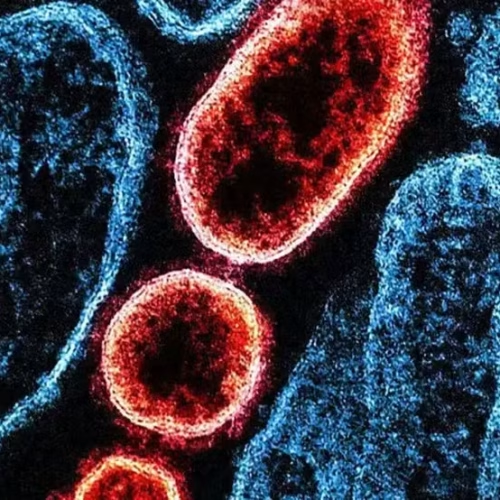

A Índia enfrenta novo surto do vírus Nipah, patógeno com alto índice de letalidade que tem afetado países na Ásia...